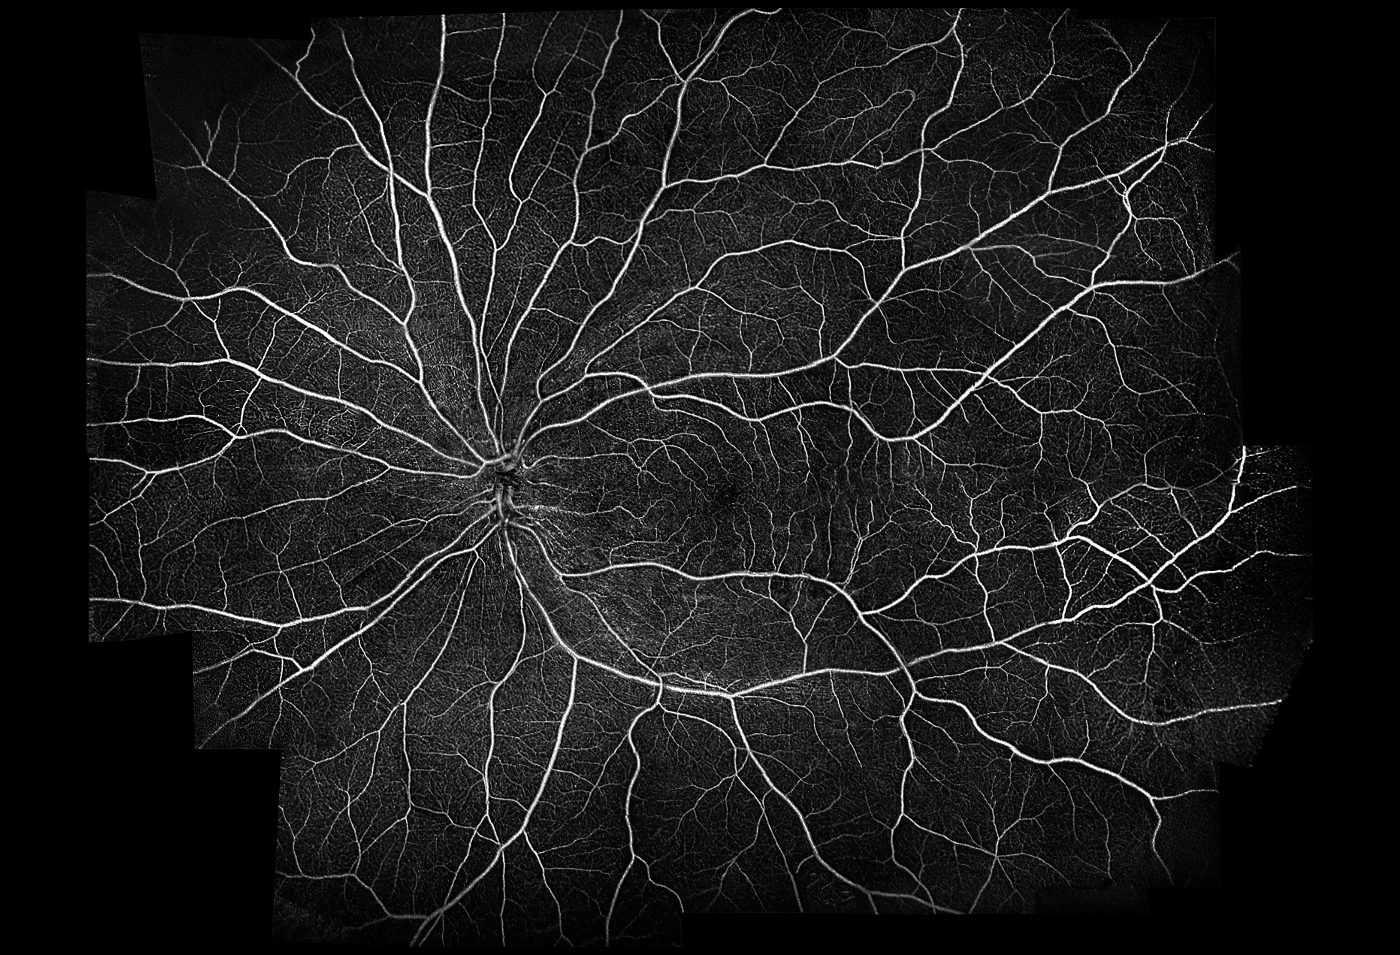

- Mosaik-Funktion

Mosaik-Scan-Bereiche:

- Vordefinierte Auto-Bereiche: 10 x 6 mm, 12 x 5 mm, 7 x 7 mm, 10 x 10 mm

- Manueller Bereich bis 18 x18 mm

Angio-Mosaik Auswertungen:

- Vaskulär und Enface: Vitreous, Superficial, RCP, Deep, Outer, Choriocapilaries, Choroid, Custom